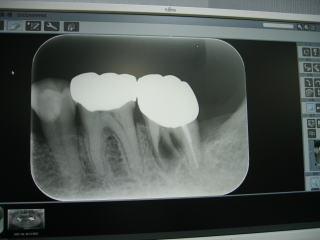

令和3年8月、平成元年の開業以来、約33年間お世話になったアナログレントゲン2台に別れを告げ、

最新式のデジタルレントゲン2台(全体のパノラマ、一部分のデンタル)を導入しました。

患者さんの被ばく量は従来の1/5〜1/10以下となり、より安全性が増しました。

なおかつ、短時間で鮮明な画像が得られ、診断や治療に大いに役立ち、患者さんにも好評です。